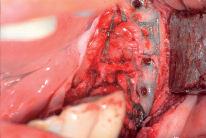

Der gewonnene autologe Knochen wurde mit Geistlich Bio Oss® und PRF gemischt, das Gitter damit aufgefüllt und eingesetzt

7 | Fixierung des aufgefüllten Gitters mit Osteosyntheseschrauben 8 | Ansicht des eingesetzten Yxoss CBR® Gitters 9 | Abdeckung des Gitters mit der GBR Membran Geistlich Bio Gide®

|

der schlechten hart und weichgewebigen Grundvoraussetzungen, konnte der Kieferkamm zufriedenstellend rekonstruiert werden

Die Augmentation des kombinierten, horizontalen und vertikalen Defekts mit Yxoss CBR®, Geistlich Bio Oss®, Geistlich Bio Gide®, autologem Knochen und PRF ermöglichte die Implantation mit hoher Primärstabilität in den rekonstruierten Bereich